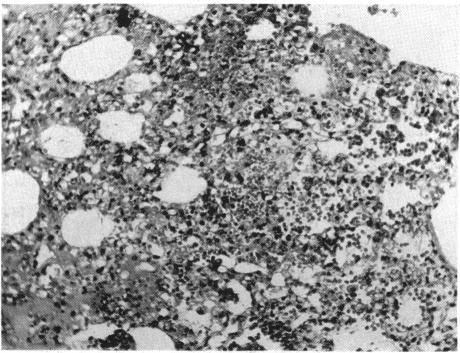

FAT EMBOLISM.

Ann Surg. 1939 Dec;110(6):1095-114. doi: 10.1097/00000658-193912000-00007.